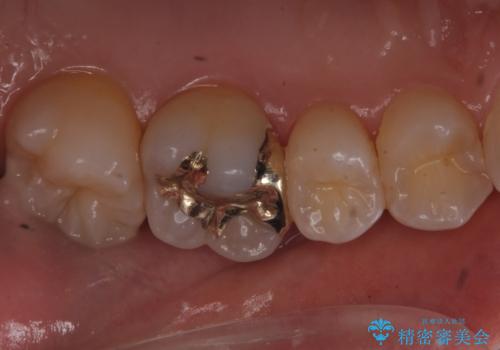

歯と歯の間の虫歯 ゴールドインレーでの修復

- フロスがよく詰まるところがあるとのことで来院されました。

検査の結果、左上の奥歯に虫歯があることが確認されました。

見た目よりも精度を優先したいとのことだったため、ゴールドインレーでの修復処置を行いました。